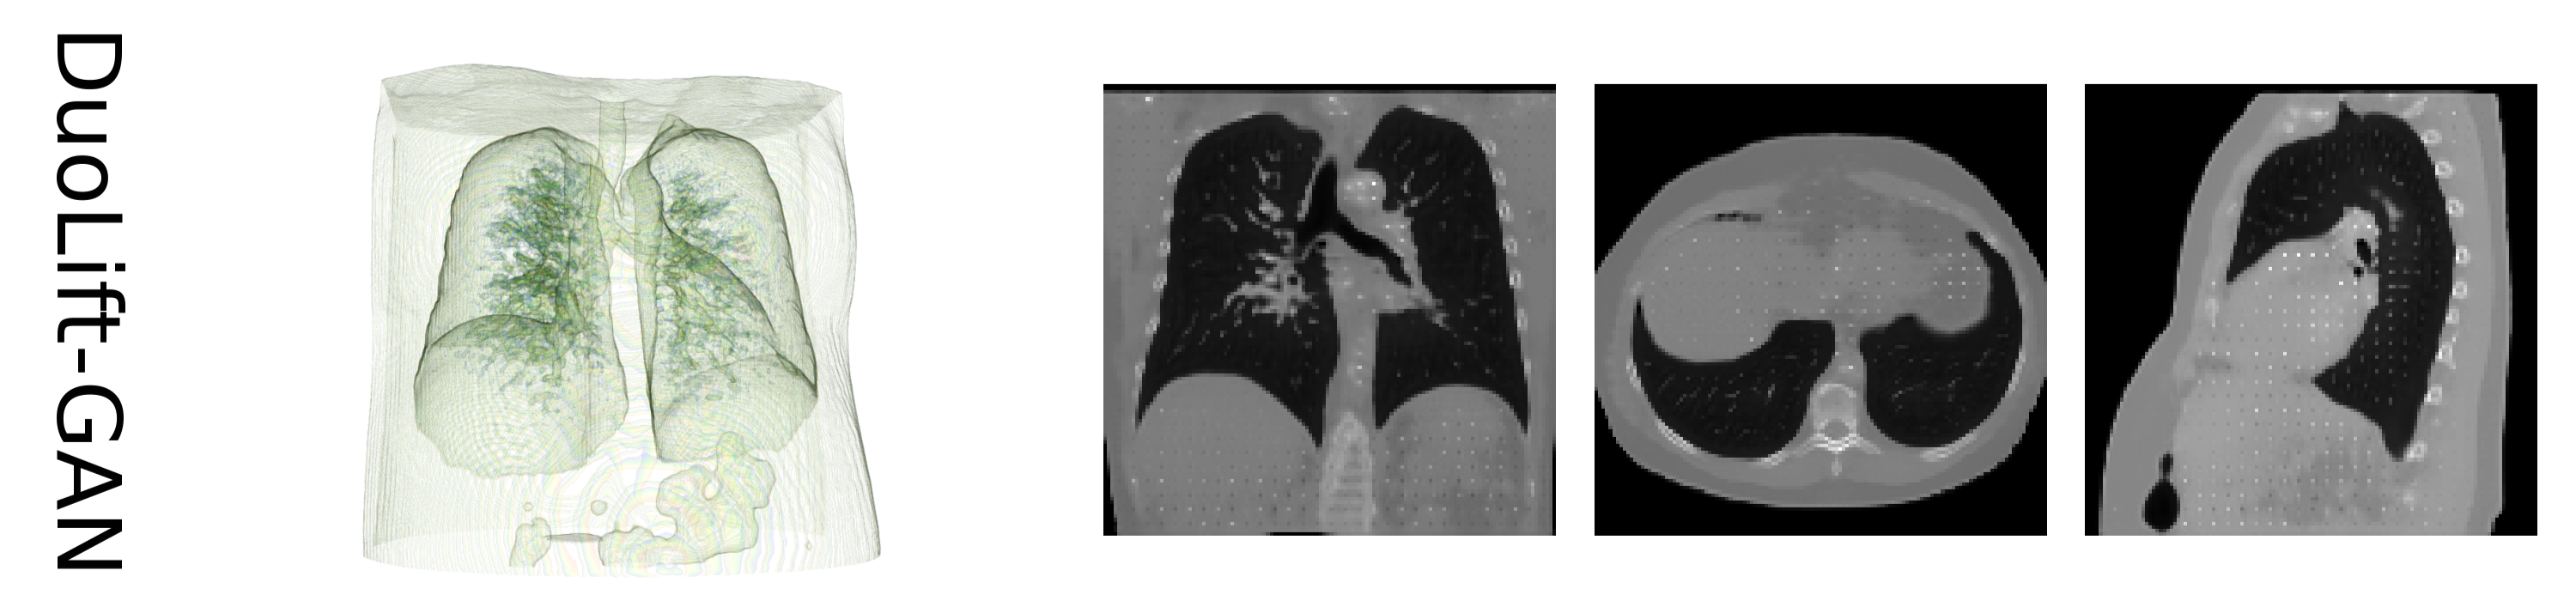

DuoLift-GAN:Reconstructing CT from Single-view and Biplanar X-Rays

Computed tomography (CT) provides highly detailed three-dimensional (3D) medical images but is costly, time-consuming, and often inaccessible in intraoperative settings (Organization et al. 2011). Recent advancements have explored reconstructing 3D chest volumes from sparse 2D X-rays, such as single-view or orthogonal double-view images. However, current models tend to process 2D images in a planar manner, prioritizing visual realism over structural accuracy. In this work, we introduce DuoLift Generative Adversarial Networks (DuoLift-GAN), a novel architecture with dual branches that independently elevate 2D images and their features into 3D representations. These 3D outputs are merged into a unified 3D feature map and decoded into a complete 3D chest volume, enabling richer 3D information capture. We also present a masked loss function that directs reconstruction towards critical anatomical regions, improving structural accuracy and visual quality. This paper demonstrates that DuoLift-GAN significantly enhances reconstruction accuracy while achieving superior visual realism compared to existing methods.

To address the challenges in 2D-to-3D reconstruction, we considered a method of lifting 2D images and features to 3D in advance to mitigate the difficulty associated with learning the mapping relationship between different dimensions. So we introduce the Duo Lift Generative Adversarial Networks (DuoLift-GAN), using a masked loss function; our model enhances detail capture by aligning the reconstruction with the target chest volume. By replicating the original 2D images and their corresponding feature maps along a specific axis multiple times, we elevate 2D images and their features into 3D representations that preserve spatial relationships and spatial coherence, resulting in more accurate 3D feature maps and improved reconstruction quality. Additionally, for precise shape and contour reconstruction, we present DuoLift-CNN, which accurately reconstructs larger anatomical structures, such as the lungs, which are suitable for capturing the overall structure rather than fine and thin structures, such as the vessels.